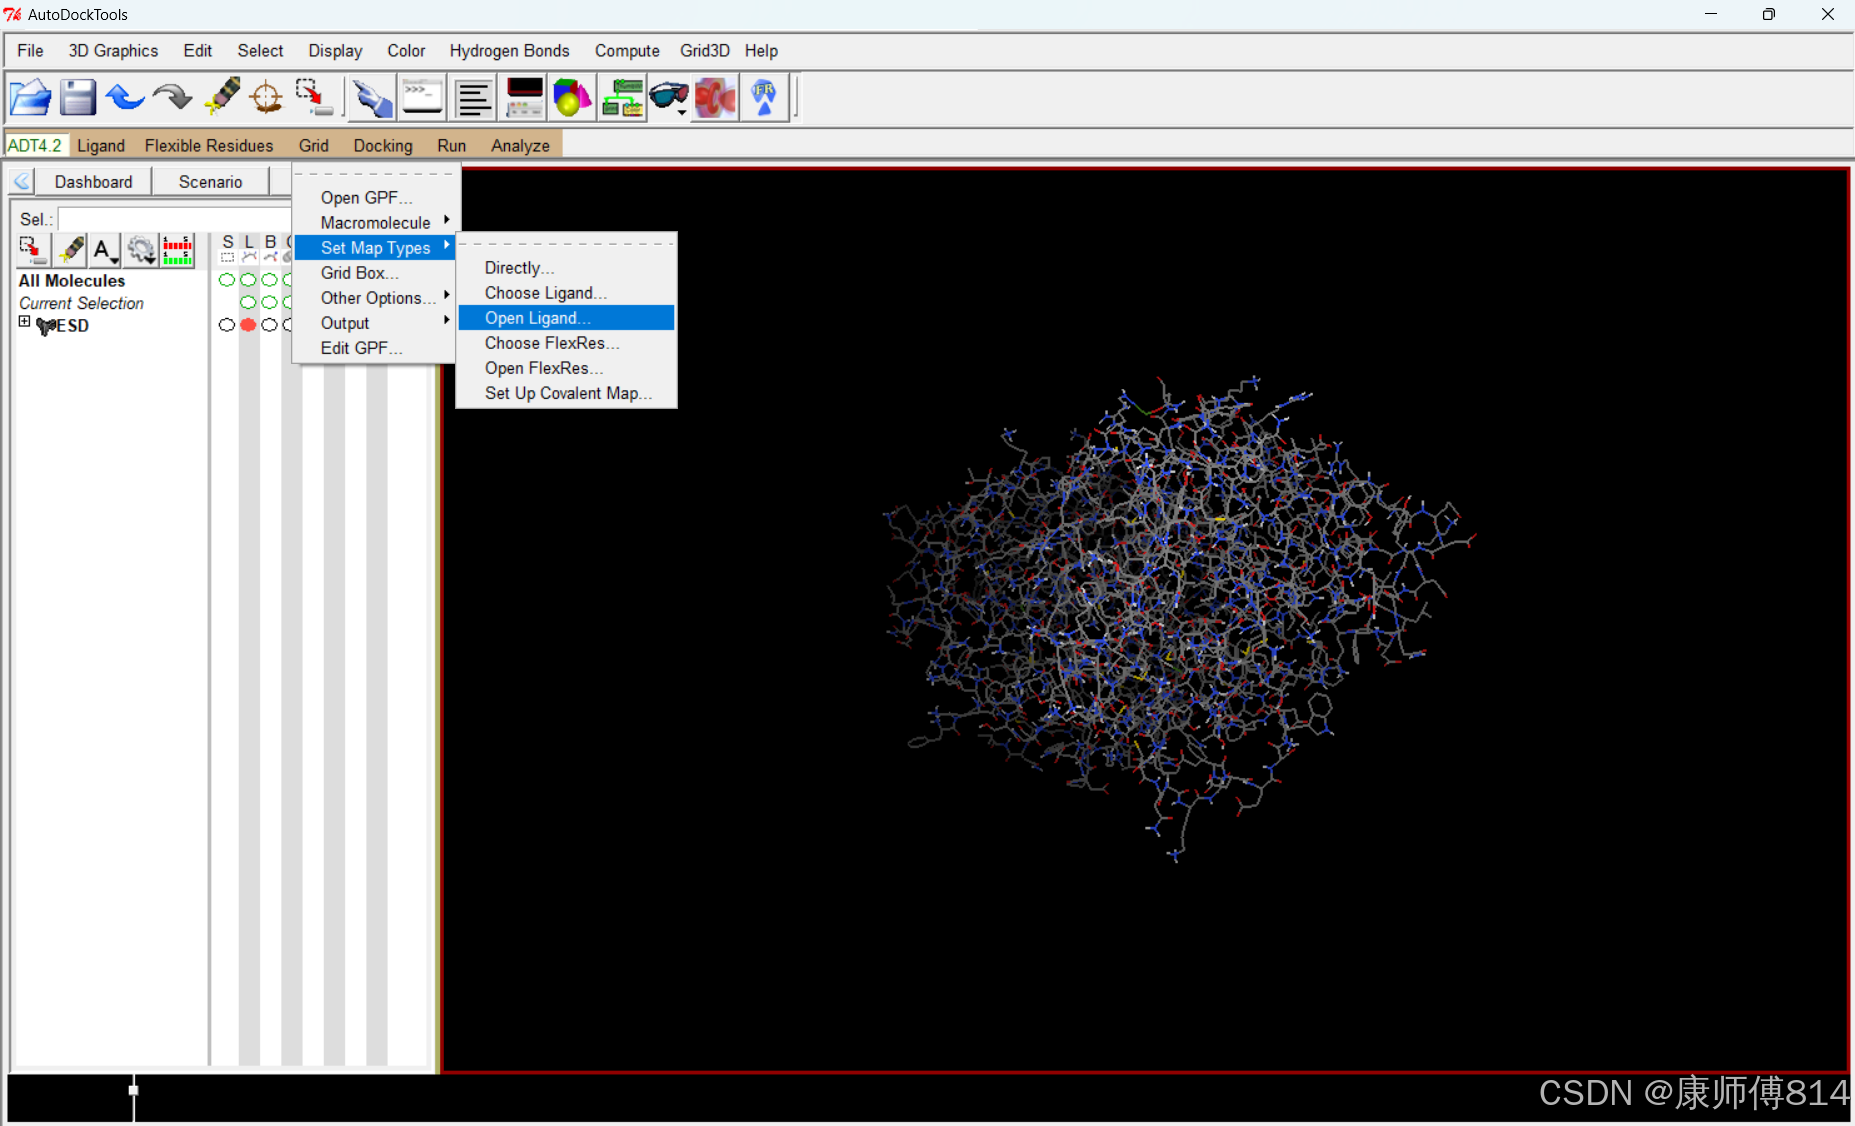

导入配体和受体文件

#点击Grid-Set Map Types-Open Ligand,选择小分子pdbqt文件